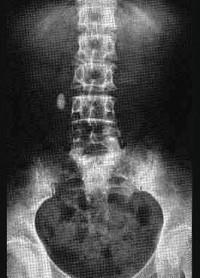

输尿管结石多发生在 ( )A、输尿管跨髂血管处B、肾盂输尿管连接处C、输尿管中1/3段D、输尿管下1/3段E、输尿管上1/3段

问题 输尿管结石多发生在 ( )

选项 A、输尿管跨髂血管处 B、肾盂输尿管连接处 C、输尿管中1/3段 D、输尿管下1/3段 E、输尿管上1/3段

答案 D